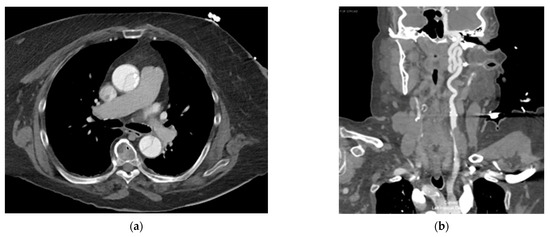

2. Detailed Case Description

3.1. Aortic Annular Rupture

3.2. Aortic Hematoma